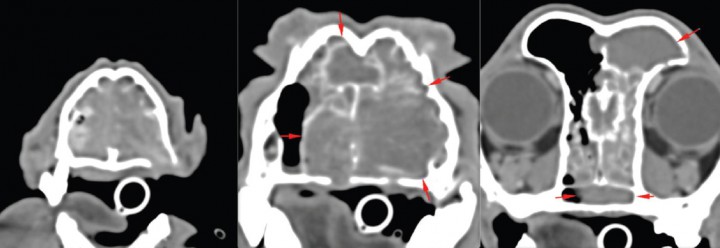

Se describe el caso clínico de una perra mestiza, castrada, de 11 años, con estridor respiratorio y epistaxis de varias semanas de evolución. En una tomografía computarizada (TC) se observó una masa que ocupaba la cavidad nasal izquierda e invadía parte de la derecha, con lisis de los huesos palatino, lacrimal izquierdo, maxilar y senos frontales, sin invasión de la lámina cribosa (estadio III, clasificación de Adams). Tras la biopsia se diagnosticó como adenocarcinoma nasal. El tumor se trató durante 5 meses con toceranib fosfato (2,7 mg/kg en protocolo de lunes-miércoles-viernes) (Palladia®, Zoetis, Madrid) y firocoxib (5 mg/kg martes-jueves-sábado; Previcox®, Merial Laboratorios, Barcelona), y aunque los propietarios observaron un beneficio clínico por mejora de los signos clínicos, la TC de control mostró enfermedad progresiva (Fig. 1), por lo que fue remitida para tratamiento de radioterapia.

<p>Imagen en TC post-contraste en plano transversal y ventana de tejido blando. Se aprecia una masa que ocupa la cavidad nasal izquierda e invade parte de la derecha, con lisis de los huesos palatino, lacrimal izquierdo, maxilar y senos frontales, sin invasión de la lámina cribosa.</p>

Imagen en TC post-contraste en plano transversal y ventana de tejido blando. Se aprecia una masa que ocupa la cavidad nasal izquierda e invade parte de la derecha, con lisis de los huesos palatino, lacrimal izquierdo, maxilar y senos frontales, sin invasión de la lámina cribosa.

<p>Imagen en TC post-contraste en plano transversal y ventana de tejido blando. (A) Al inicio del tratamiento con radioterapia. (B) A los 3 meses del tratamiento, donde se observa una marcada reducción del volumen tumoral.</p>

Imagen en TC post-contraste en plano transversal y ventana de tejido blando. (A) Al inicio del tratamiento con radioterapia. (B) A los 3 meses del tratamiento, donde se observa una marcada reducción del volumen tumoral.